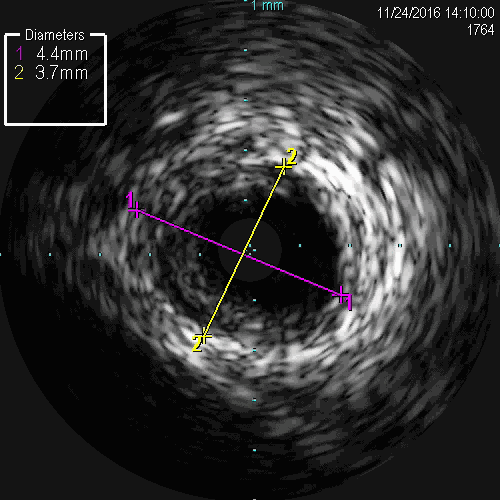

LAD-IVUS

LAD中段既往支架膨胀不良

导丝主要位于真腔

LCX-IVUS

LCX远端真腔,近端内膜下

IVUS结果